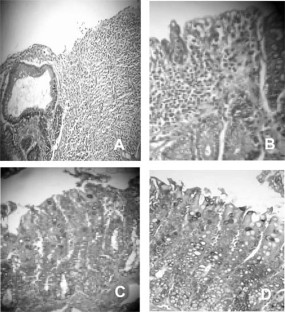

Fig 1.

Fig 2.

Fig 3.

Fig 4.